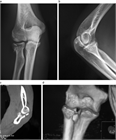

1. 橈骨頭骨折、橈骨頸部骨折の解剖学的特徴を把握する。

1. 橈骨頭骨折、橈骨頸部骨折は上腕骨小頭と橈骨頭が衝突して生じる。

1. 成人では橈骨頭に加え橈骨頚部も骨折しやすいが、小児では多くが橈骨頚部骨折である。